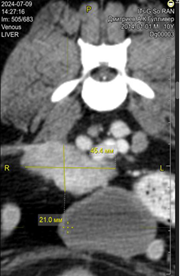

Рис. 8. Общее состояние животного № 8 до (a) и после (b) ГНЗТ; данные КТ до ГНЗТ (с, d) и после ГНЗТ (е, f)

По данным КТ от 23.02.2024 г. (рис. 8c, 8d) до ГНЗТ визуализируется опухоль простаты размерами 1,1×1,7×1,4 см. В динамике: КТ от 11.05.2024 г. (рис. 8e, 8f) показала распространение опухоли на мочевой пузырь, особенно в области шейки мочевого пузыря и треугольника, при этом опухоль простаты уменьшилась в размерах до 0,5×0,9×0,6 см.

Было отмечено, что сразу после облучения побочных эффектов не наблюдалось. Животное № 8 оставалось активным и энергичным. Через неделю после ГНЗТ на облученных участках появились покраснение, выпадение волос, болезненность при прикосновении. Частота мочеиспускания уменьшилась. Однако через два месяца после ГНЗТ животное потеряло 1 кг веса, аппетит снизился. Во время дефекации отмечалось натуживание, а диаметр каловых масс стал меньше. КТ через три месяца после ГНЗТ показала, что опухоль распространилась на мочевой пузырь, что побудило принять решение о проведении второго сеанса ГНЗТ в перспективе.